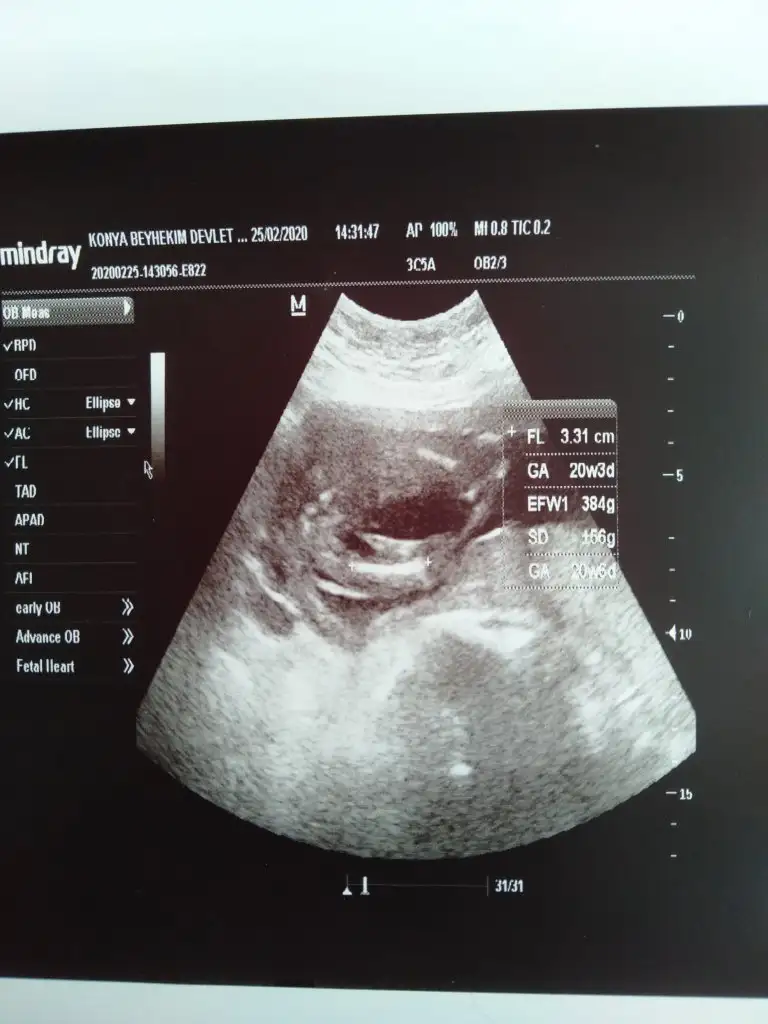

S.a Ikra meyra Ikra meyra cnm ultrason resmini alınca sana aticaktm bugüne kısmetmiş ben biseyy anlamadm ya görüntü net değil ya da ben tecrubesizim sana zahmet bakar msn sence cinsiyet ne bugün sırf cinsiyet için farkli doktora gittim 🤭☺️🤔

S.a Ikra meyra Ikra meyra cnm ultrason resmini alınca sana aticaktm bugüne kısmetmiş ben biseyy anlamadm ya görüntü net değil ya da ben tecrubesizim sana zahmet bakar msn sence cinsiyet ne bugün sırf cinsiyet için farkli doktora gittim 🤭🤔

Yok cnm gitmedim dhaa Mart 11 de ayrıntılı ultrason tarihim daha öncesinde doktorum tahmin yaptı ama net olmayınca emin olamadm ultrason ftgrafi da hiç istemedim onlarda vermedi herhlde ondan geç kaldm ☺️🤭